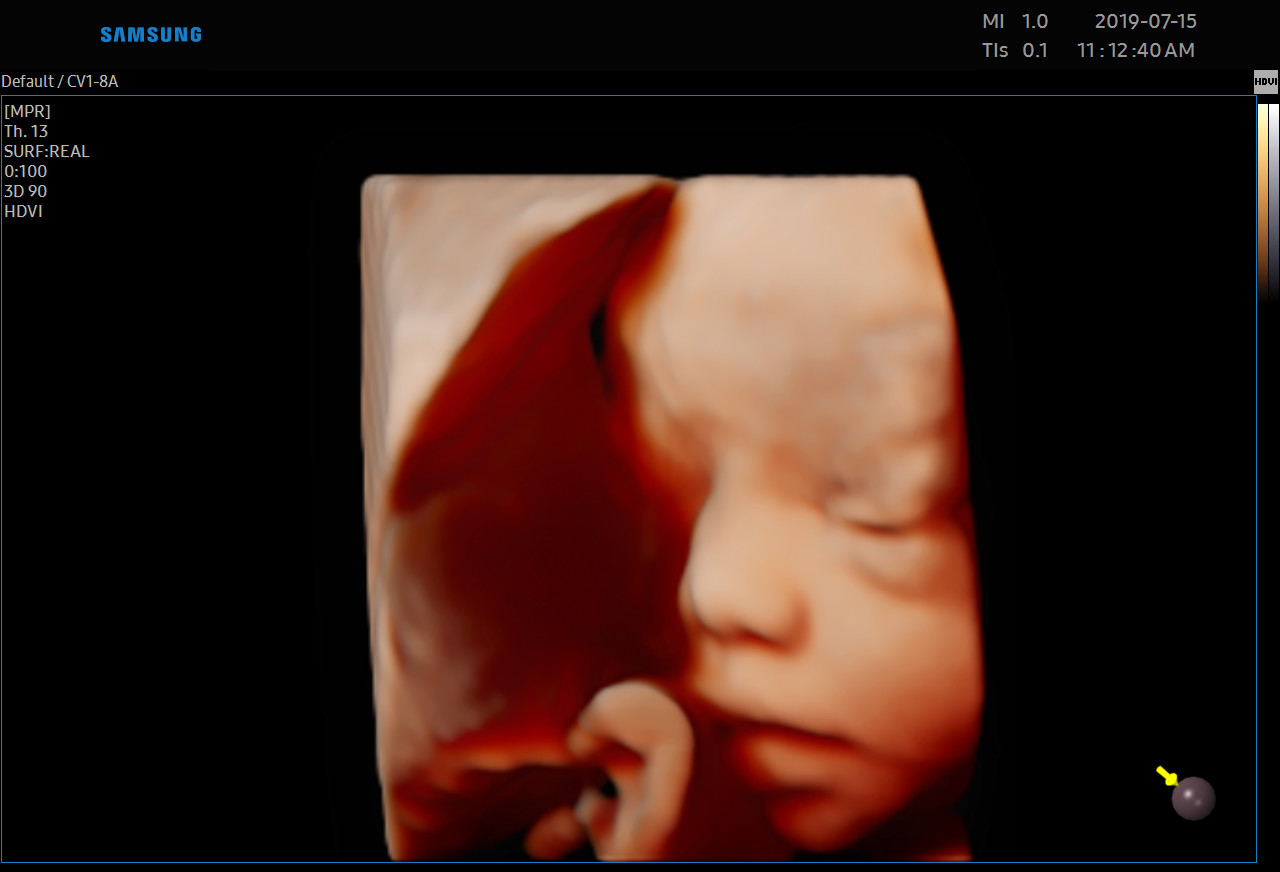

Każdą kobietę w ciąży otaczamy kompleksową opieką, czuwając nad jej zdrowiem oraz prawidłowym rozwojem płodu. Podczas regularnych wizyt, zlecamy odpowiednie badania laboratoryjne. Korzystając z najnowszej generacji aparatu USG, przeprowadzamy bardzo dokładną diagnostykę obrazową – łącznie z USG 3D/4D płodu.

• Najnowsza generacja aparatu USG pozwala na przeprowadzanie dokładnej diagnostyki obrazowej, diagnostyki przepływów (Doppler).